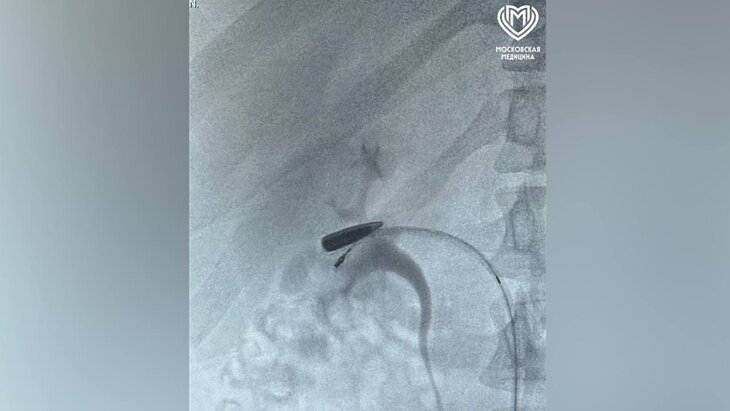

Фото: телеграм-канал "Московская медицина"

Специалисты флагманского центра Института Склифосовского спасли пациента от пули, которая двигалась по вене. Об этом сообщает пресс-служба столичного Депздрава.

Пострадавшего с огнестрельным ранением над ключицей доставили в центр на вертолете. Врачи выяснили, что пуля мигрировала и остановилась в правой почечной вене, что является очень редким случаем.

"Пациента срочно прооперировали: хирурги выделили пораженные сосуды, временно пережали их всего на 6–7 минут, извлекли пулю и восстановили кровоток", – сообщили в пресс-службе департамента.

В итоге почка не пострадала, пациент находится в стабильном состоянии.